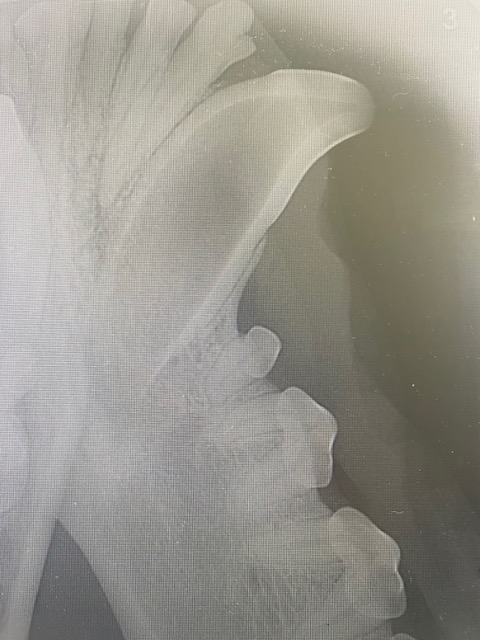

The above tooth has had a root canal procedure performed. You can see the radiopaque filler (in this case flowable gutta percha with a GP point) fills the whole canal, and can be compressed down to where the pulp chamber ends.